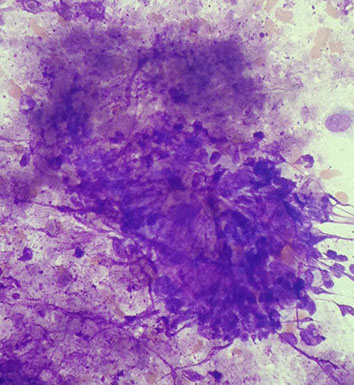

Adenoid Cystic Carcinoma (ACC)

Variably sized, often large , 3-D, acellular hyaline matrix globules and linear branching structures

Matrix is acellular with sharp borders (“cookie-cutter” like)

Basaloid cells

(Arrows show transparent hyaline globules on figure to left)